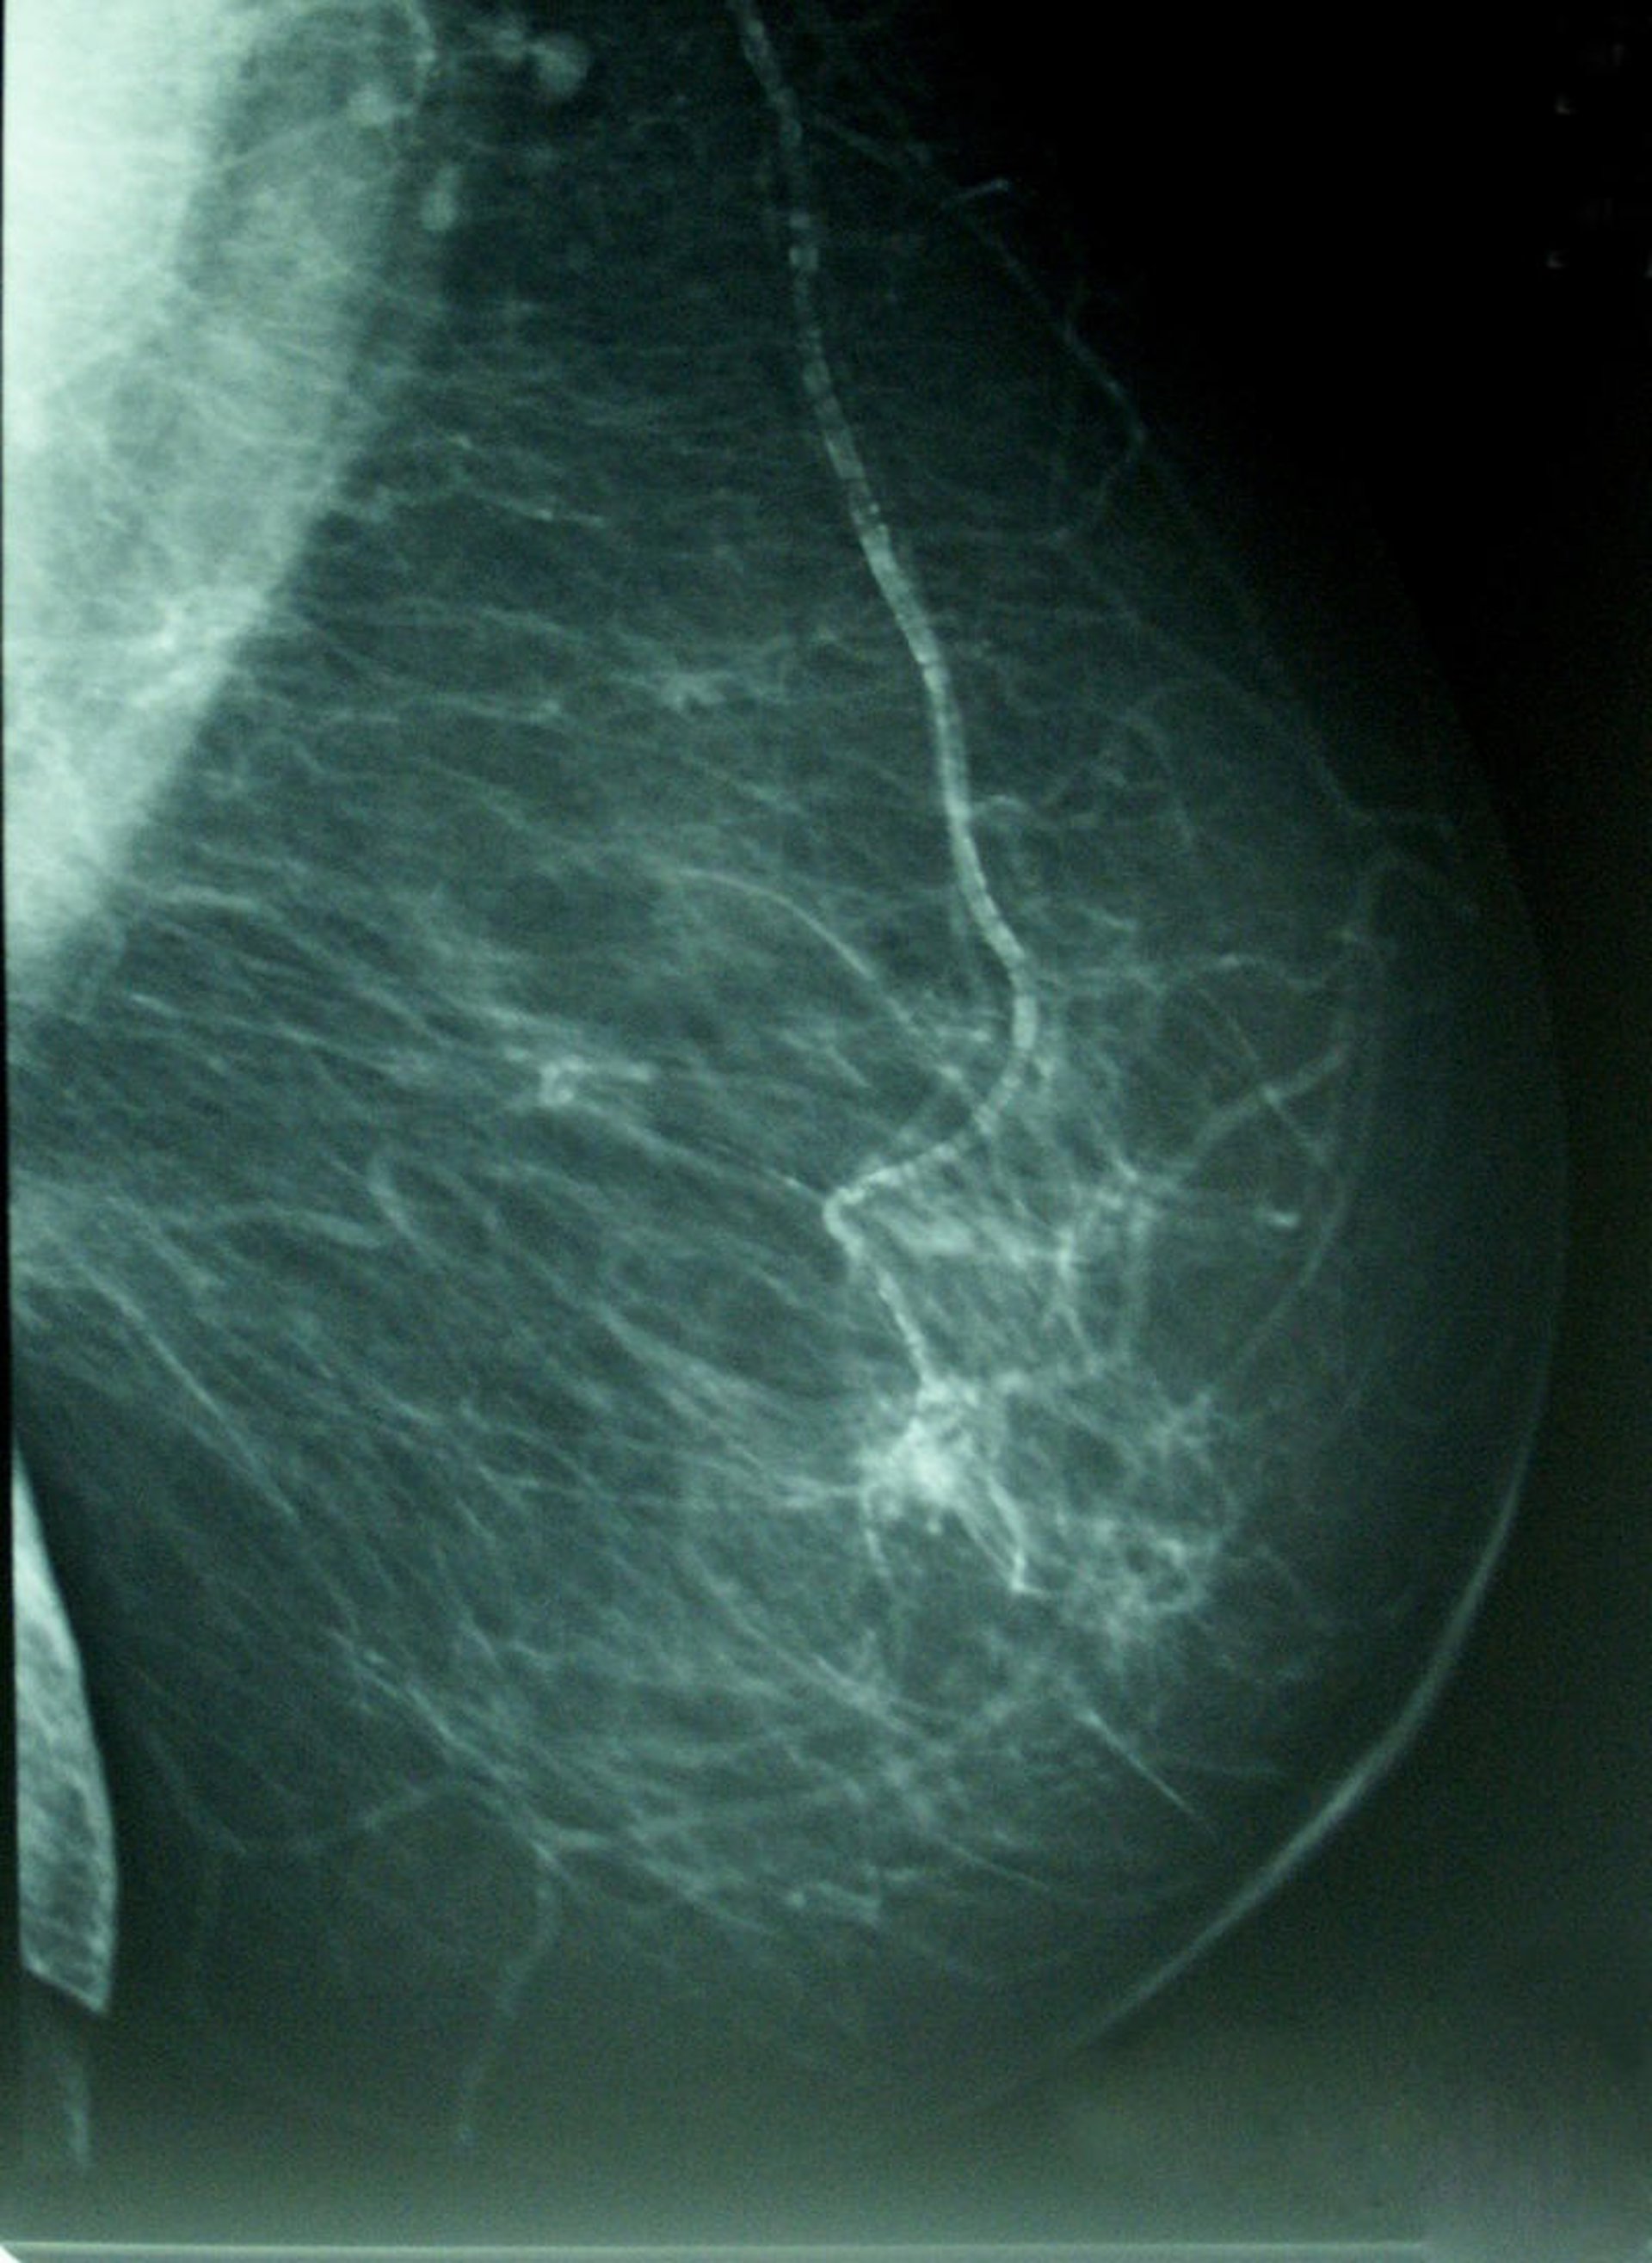

Las nacidas de madres con más de 39 años y aquellas que eran más altas y delgadas que la mayoría antes de la pubertad presentan mayor densidad mamaria y, con ello, mayor riesgo de cáncer de mama, según un estudio liderado por investigadores del Instituto de Salud Carlos III (ISCIII).

La primera autora del estudio e investigadora del Centro Nacional de Epidemiología del ISCIII, la doctora Virginia Lope, explica a la plataforma de información científica SINC que "la exposición acumulada a hormonas y factores de crecimiento en las primeras etapas de la vida, cuando las mamas empiezan a desarrollarse, condiciona la composición del tejido mamario y la probabilidad de desarrollar un tumor de mama en la etapa adulta".

El estudio, publicado en la revista 'Breast Cancer Research and Treatment', explora la influencia de determinadas características con dicha densidad - la proporción de tejido radiológicamente blanco en la mamografía-, que es reconocido como un marcador de riesgo de cáncer de mama.